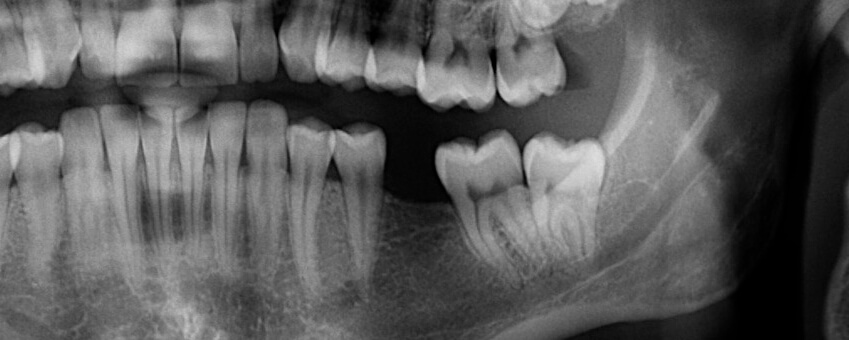

A tooth may require extraction for a variety of reasons. If the tooth is impacted in the gumline (particularly common with wisdom teeth), if there are serious crowding issues, or if the tooth is too damaged, rotted, or loose to be saved with root canal treatment, Dr. Foroutan may determine that extraction is the best option. After the recovery period is over, it will be time to begin taking the prosthodontic or orthodontic steps needed to fill in your smile.